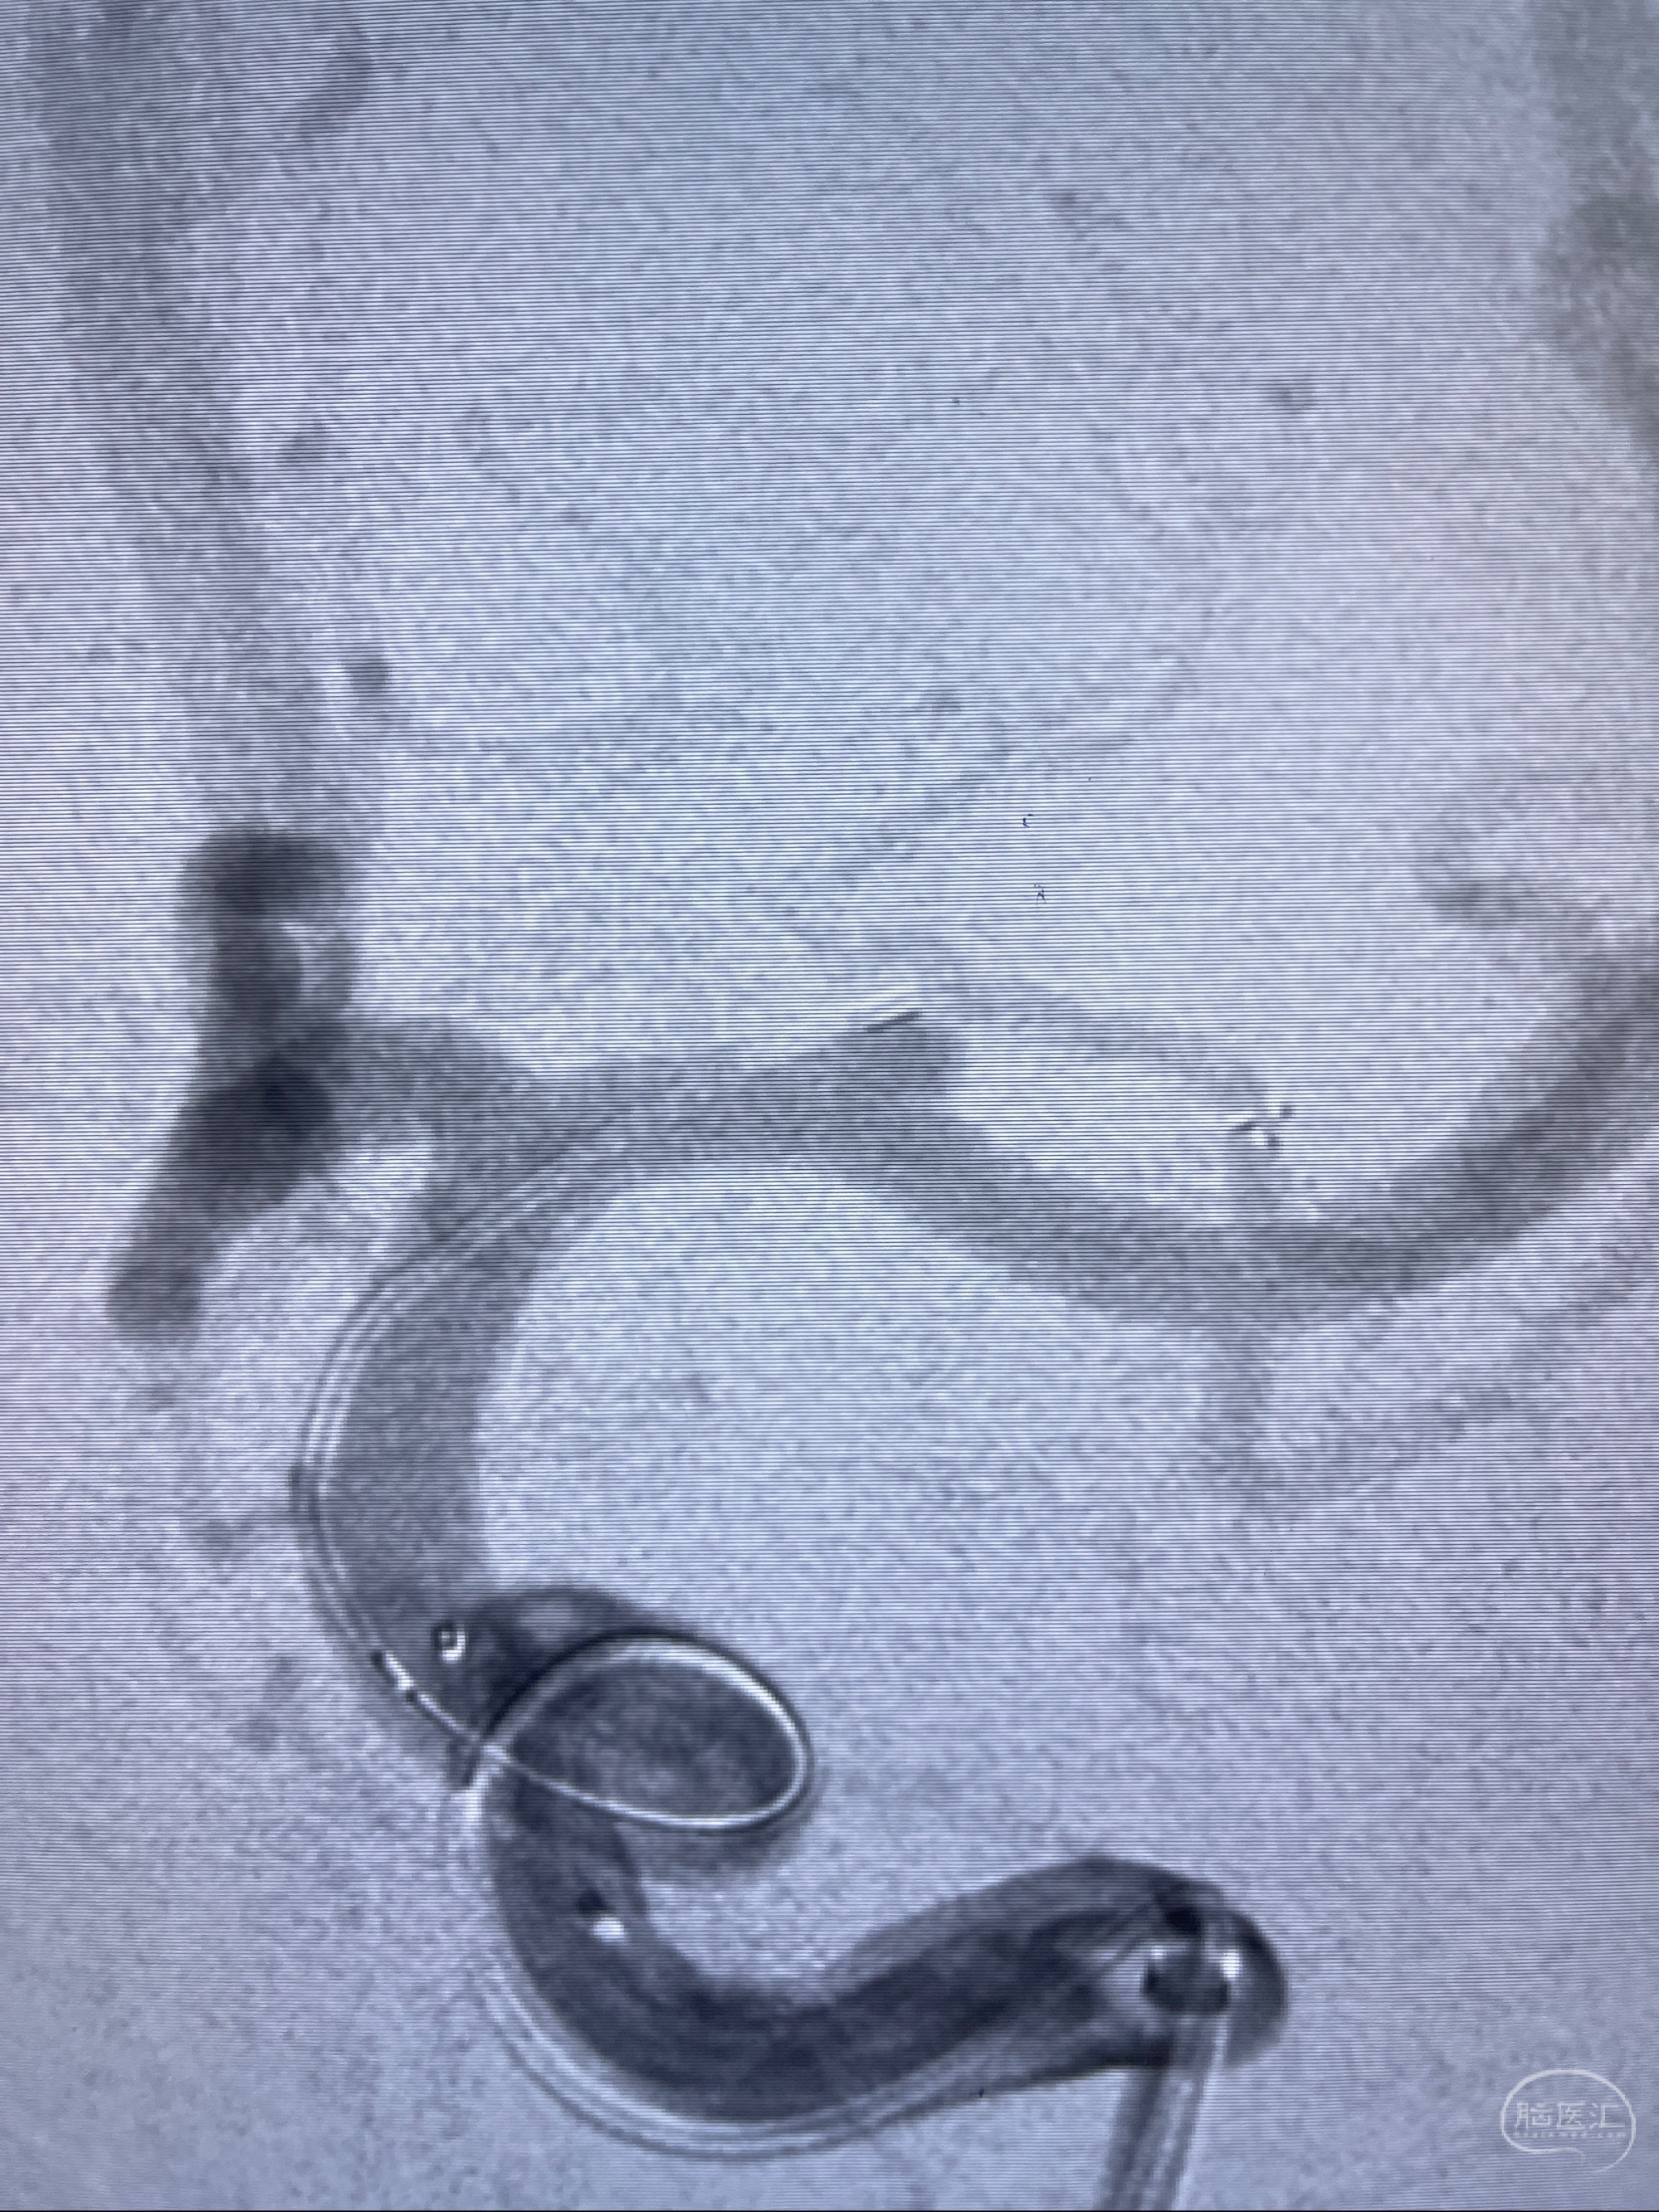

2023-08-14DSA:

左侧大脑中动脉动脉瘤,约2.6-2.8-3.4-2mm大小(瘤颈部、瘤体部、瘤高)

1.左侧大脑中动脉动脉瘤,约2.6-2.8-3.4-2mm大小(瘤颈部、瘤体部、瘤高)

2.外科手术夹闭or介入支架辅助栓塞